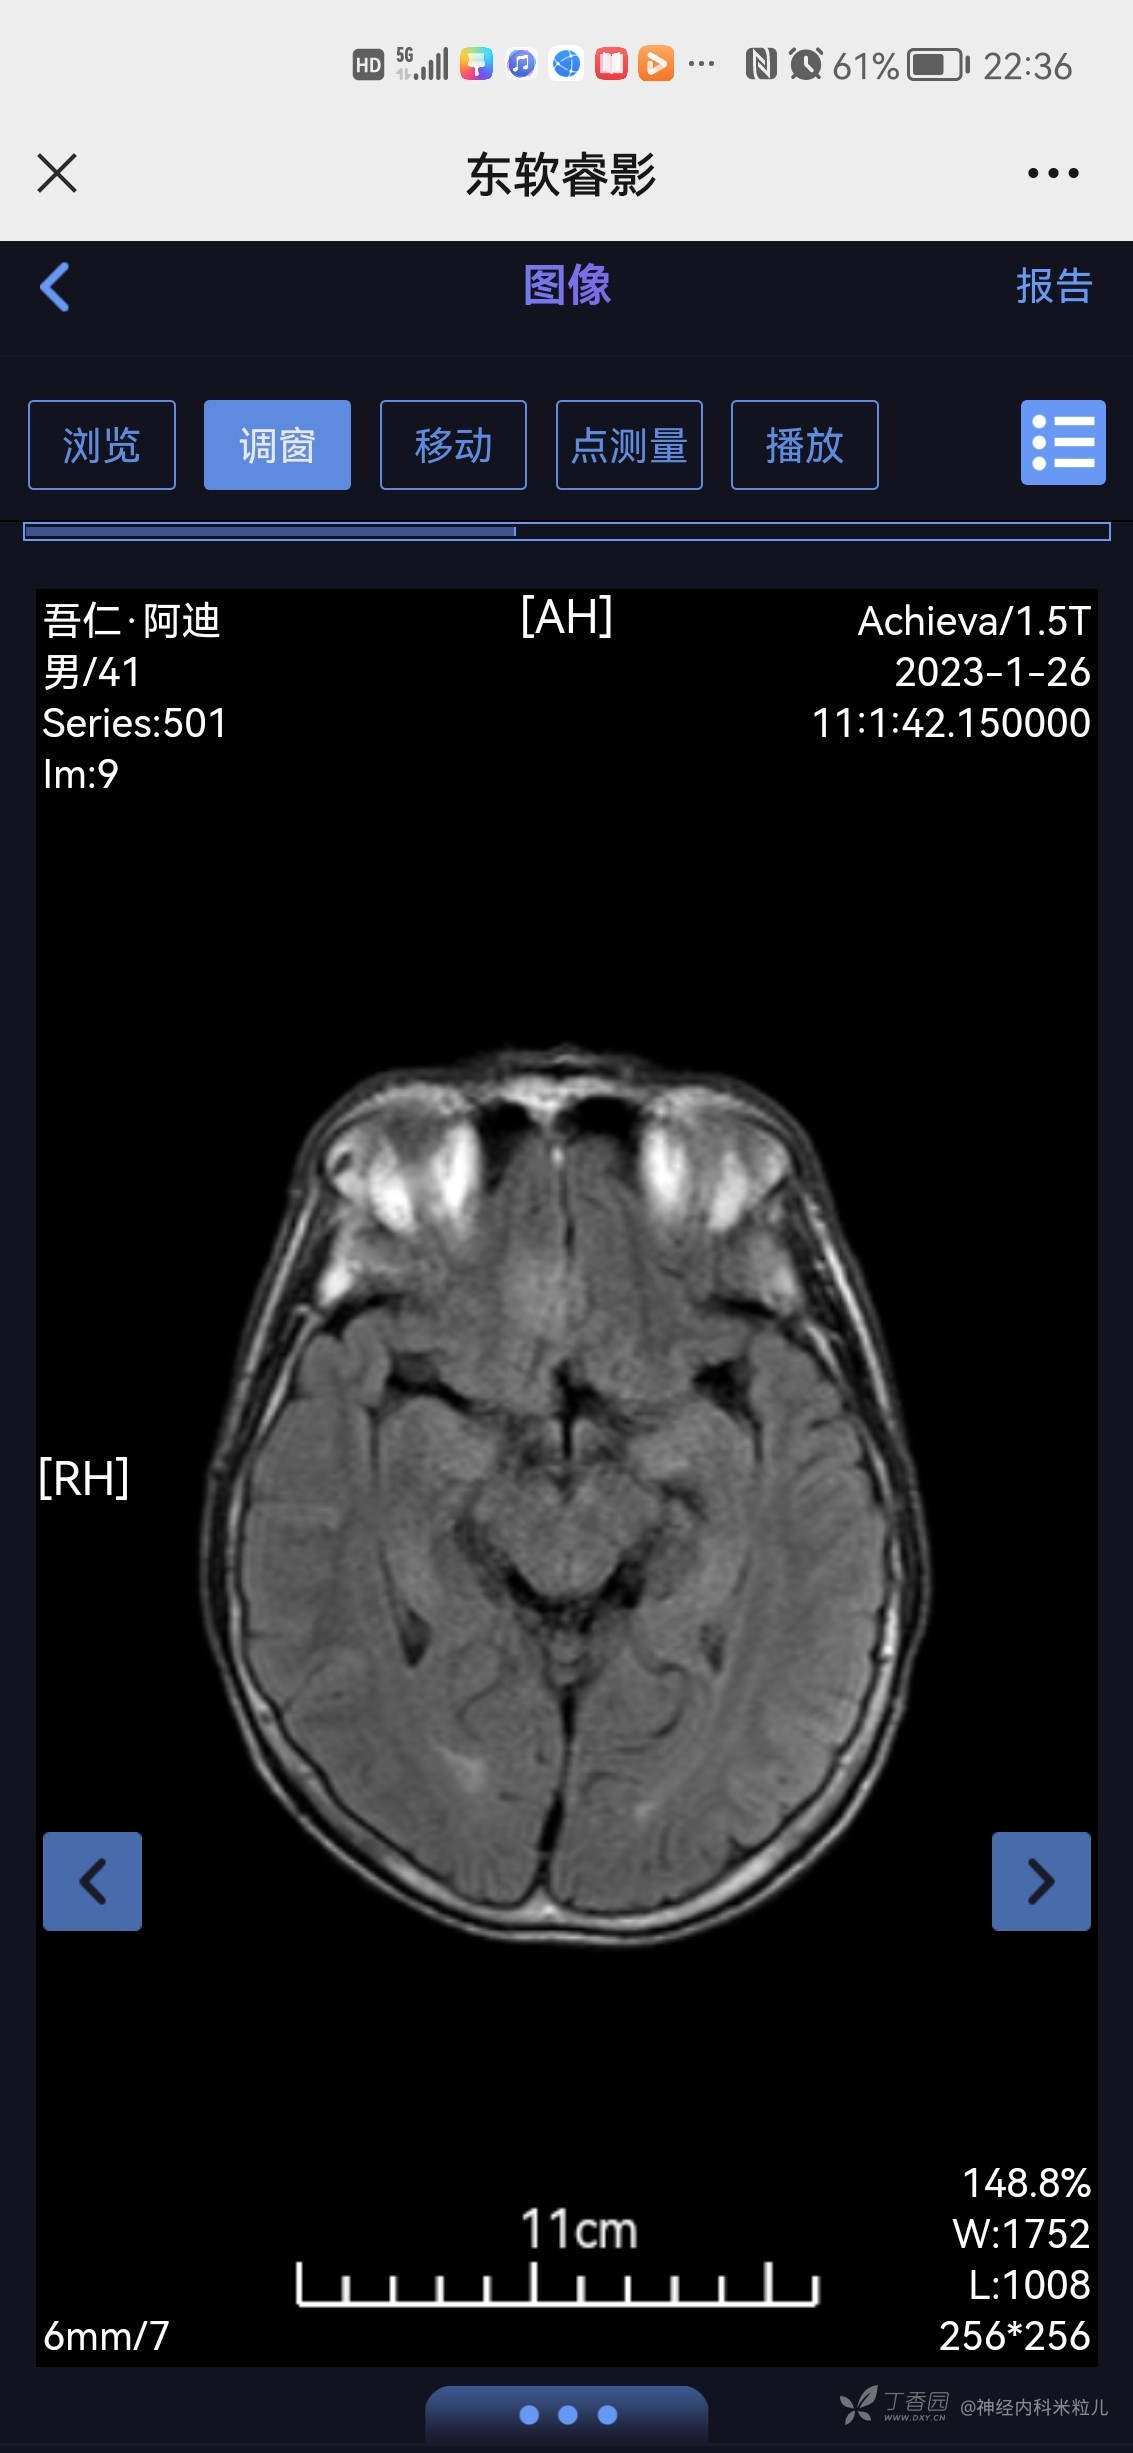

2023年1月18日我院头颅核磁提示:颅内多发异常信号,考虑:感染性病变,建议增强检查。}